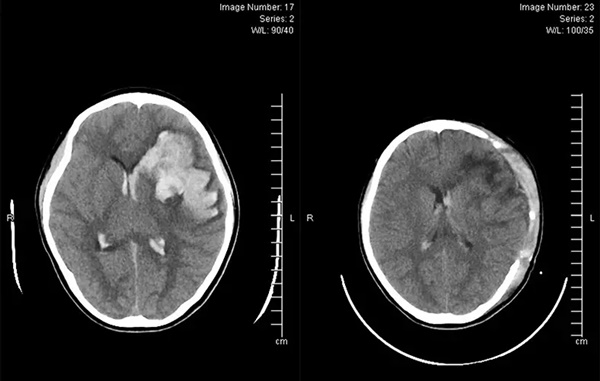

Hình ảnh CT scaner sọ não của bệnh nhân trước và sau phẫu thuật xuất huyết do vỡ khối thông động tĩnh mạch não

1 giờ trước khi nhập viện, bệnh nhi Nguyễn L.Q.N, (13 tuổi, trú tại TP Hạ Long, Quảng Ninh) có tình trạng co giật, giảm ý thức. Cấp cứu tại Bệnh viện Bãi Cháy, N. được thăm khám lâm sàng, cận lâm sàng, kết quả chụp Ctscaner sọ não cho thấy hình ảnh xuất huyết não.

Các bác sĩ đã hội chẩn, kết luận bệnh nhân xuất huyết não do vỡ khối thông động tĩnh mạch não (AVM). Tiên lượng tình trạng bệnh nhân nặng, nguy cơ tử vong cao, các bác sĩ đã tiến hành phẫu thuật mở sọ cắt bỏ khối dị dạng AVM, giải áp, lấy máu tụ.